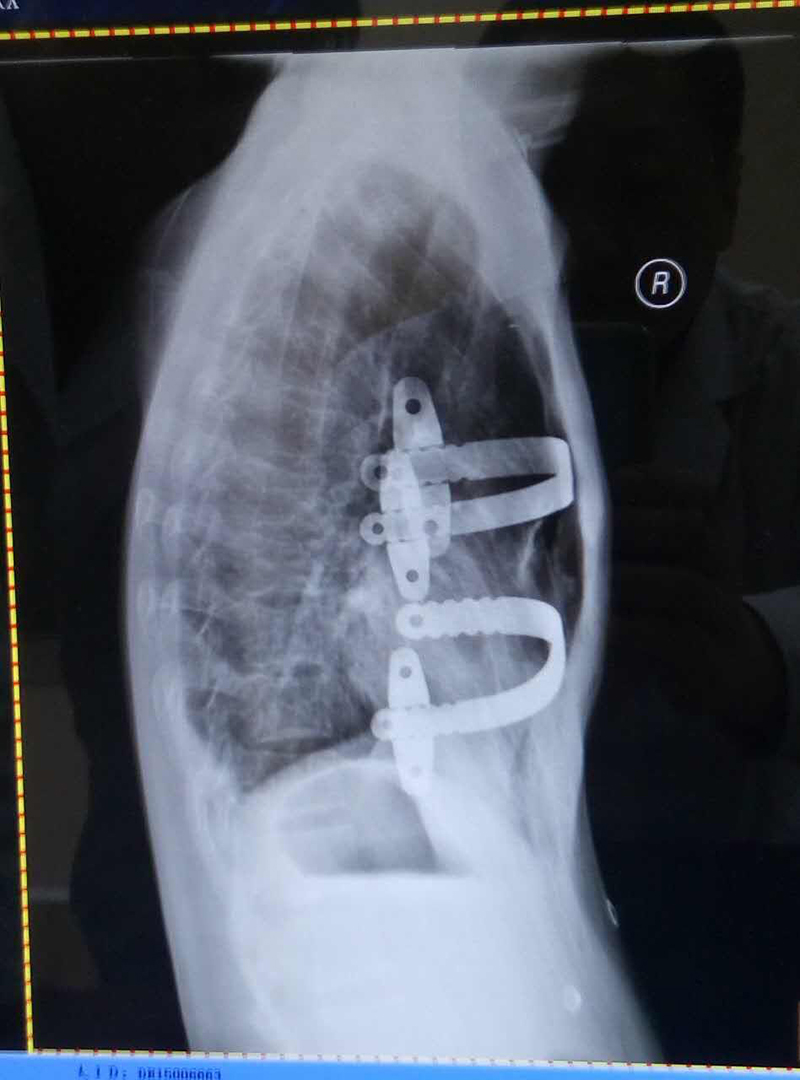

漏斗胸nuss纠正术

图片尺寸2340x1080